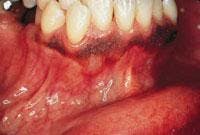

CASE 8

Smokeless tobacco keratosis

1. Where is the smokeless tobacco keratosis likely to occur?

a. mucobuccal fold area

b. dorsal tongue

c. hard palate

d. gingiva

2. What is the clinical appearance of the smokeless tobacco keratosis?

a. white color

b. raised or flat contours

c. smooth, granular or corrugated

d. any of the above

3. What is the recommended treatment for the smokeless tobacco keratosis?

a. surgical removal

b. radiation therapy

c. discontinue use of product

d. none of the above